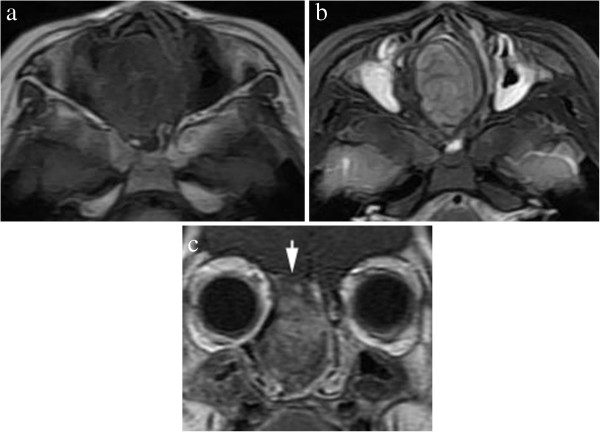

Figure 2.

MR Imaging of sinonasal cavity. (a) An axial T1-weighted MRI revealed a mildly hypointense mass in the right nasal cavity. (b) An axial T2-weighted MRI showed a well-defined hyperintense mass and strong signal in both maxillary sinuses. (c) A coronal contrast-enhanced T1-weighted MRI showed striking enhancement of the mass, extending into the anterior fossa with intact dura.

A 5-year-old boy was admitted to our hospital for evaluation of nasal obstruction, recurrent sinusitis, and noisy breathing over a period of 4 years. The child had normal nutrition and development. Physical examination revealed a smooth, purple, non-tender mass attached to the roof of the right nasal cavity. No palpable cervical lymphadenopathy was identified. The remainder of his medical and family history was unremarkable. A CT scan revealed an oval-shaped, well-defined homogeneous soft-tissue mass in the right nasal cavity. The mass measured 2.5 × 3.6 × 4.3 cm and involved the ethmoid sinus, extending up to the cribriform plate and the anterior cranial fossa with evidence of bony erosion of the cribriform plate. Tumor density was measured in regions of interest in different slices and ranged from 33 to 36 Hounsfield Units (HU) before contrast injection; it was strikingly enhanced after injection, to a range of 64 to 69 HU (Figure 1). MRI demonstrated a well-demarcated homogeneous mass extending to the anterior cranial fossa in the right nasal cavity. The mass had low signal intensity on T1-weighted images and mixed high signal intensity on T2-weighted images, with striking inhomogeneous enhancement (Figure 2). No calcification, cystic component, or definite dural enhancement was identified. The right nasal cavity was dilated. The middle and inferior turbinates were medially compressed and the nasal septum was deviated to the left, but the mass did not invade adjacent structures. A biopsy was performed and the pathology report was consistent with NCMH. Operative findings revealed a well-defined mass attached to the anterior skull base, and a subtotal resection was performed. Histopathologically, the mass was composed mainly of irregular islands of chondroid tissues and mesenchymal elements such as spindle cells in a myxoid stroma (Figure 3). At present, a follow-up CT at 3 years revealed no recurrence.